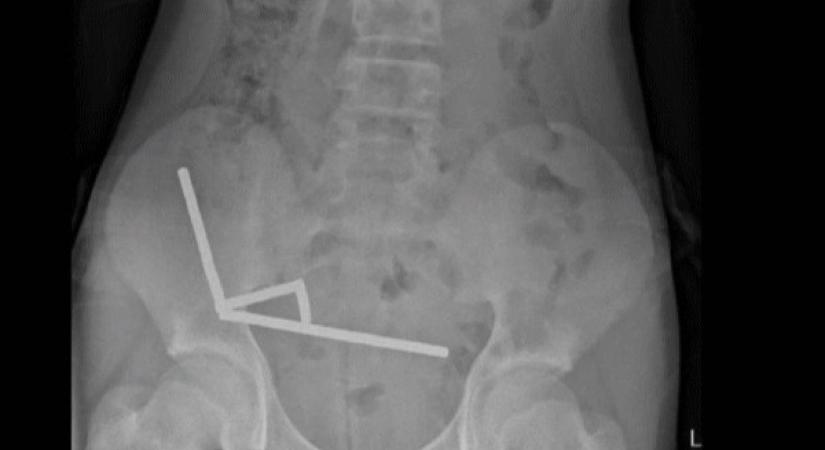

Csaknem 200 Temuról rendelt mágnest nyelt le egy 13 éves fiú, elvesztette a bélrendszere egy részét Ma 14:24 Népszava bélrendszer Ágnes Hogy mi vette rá erre, az nem derült ki. Elolvasom a cikket >> - Hirdetés -